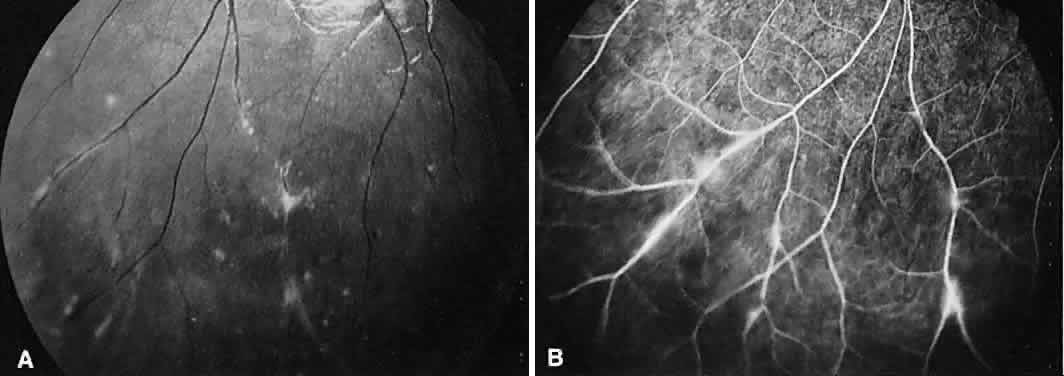

Multifocal choroiditis may mimic the typical clinical findings of presumed ocular histoplasmosis syndrome (discussed later) and has the additional finding of anterior chamber and vitreous cells. Multiple yellow or gray acute choroidal lesions measuring 50 to 350 μm, periphlebitis, and occasionally retinal neovascularization can be seen. Marked pigmentary disturbances may be seen in the chronic phase (Fig. 11A).

Fig. 11. Multifocal choroiditis. A. Fundus photograph showing pigmentary disturbances. B. Multiple areas of hypofluorescence and hyperfluorescence representing chorioretinal scars with associated atrophic areas. C. Indocyanine green angiogram shows multiple areas of hypofluorescence around the disc, the macula, and the midperipheral fundus. Some of these areas are not visible clinically or on fluorescein angiogram.

On fluorescein angiography (see Fig. 11B), the punched-out lesions show the typical window defects. Acute lesions block early choroidal fluorescence and stain late. Cystoid macular edema and prolonged arteriovenous circulation times may be seen.39 Progressive subretinal fibrosis is a reported sequela that presents as multiple stellar zones of subretinal fibrosis. This fibrosis can be surrounded by multiple atrophic punched-out lesions (Fig. 12).40

Fig. 12. Multifocal choroiditis with subretinal fibrosis in a 26-year-old woman. A and B. Color photographs show hypopigmented lesions representing subretinal fibrosis involving both macular lesions. Multiple punched-out lesions surround the bands of fibrosis. C. Staining of the large stellate fibrous lesion can be seen in the left macula. There are multiple punched-out lesions above and below the macular zone. Leakage from the optic disc and its vessels can also be seen.

ICG angiography shows large hypofluorescent spots in the posterior pole measuring 200 to 500 μm, which did not usually correspond to clinically or fluorescein angiographically detectable lesions (see Fig. 11C). Smaller hypofluorescent spots, less than 50 μm, also may be seen in the posterior pole. Both large and small lesions are best seen in the later phases of the angiogram. Confluent hypofluorescent areas may be seen around the optic nerve in patients reporting an enlarged blind spot on visual field testing.41